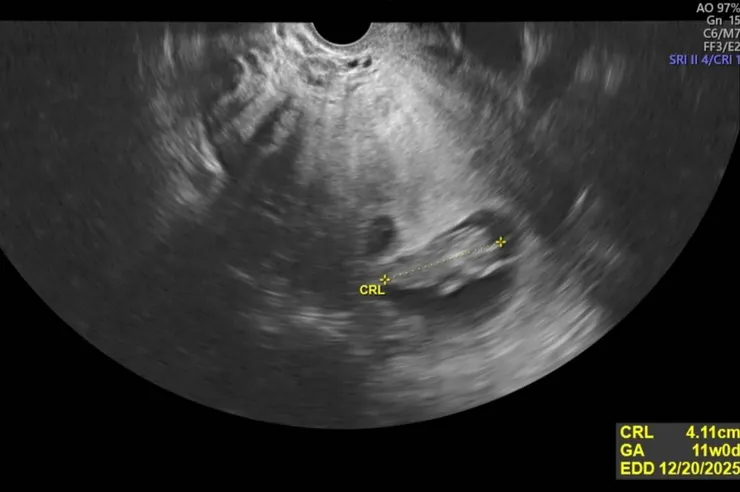

11 週的小女

去年主要可以分為三個階段,以六月底至九月底的遊學做區分。上半年一方面在研究所上課及參加研討會發表論文外,另一方面在汗得學社「文化資產之建築認識與永續再利用創意夢想」系列課程教授「文化資產概論」,並準備遊學相關事宜(包含上德文課)。下半年一方面開始找工作面試及考博士資格考(還剩一科),另一方面領了普發一萬元後,報了托育人員課程,為當爸做準備,年底喜迎小女誕生。

小女的誕生,完全轉向另一種生活與重心。像宇宙大爆炸後,從無限擴張後返回奇異點,回到最原初的狀態。除了生活重心與作息的改變外(小女先吃我再吃,小女先睡我再睡),最可貴的是創造了許多獨有的情境,讓那些埋藏在過往的記憶得已顯現。如小女目前還無法睡過夜,有時候白天睡比較多晚上睡比較少,老媽說這是遺傳到爸爸(我),說我前三個月也是晚上哭白天睡。要不是生命的延續創造了這些情境,我可能永遠不會知道那些「關於我的」老媽的記憶。